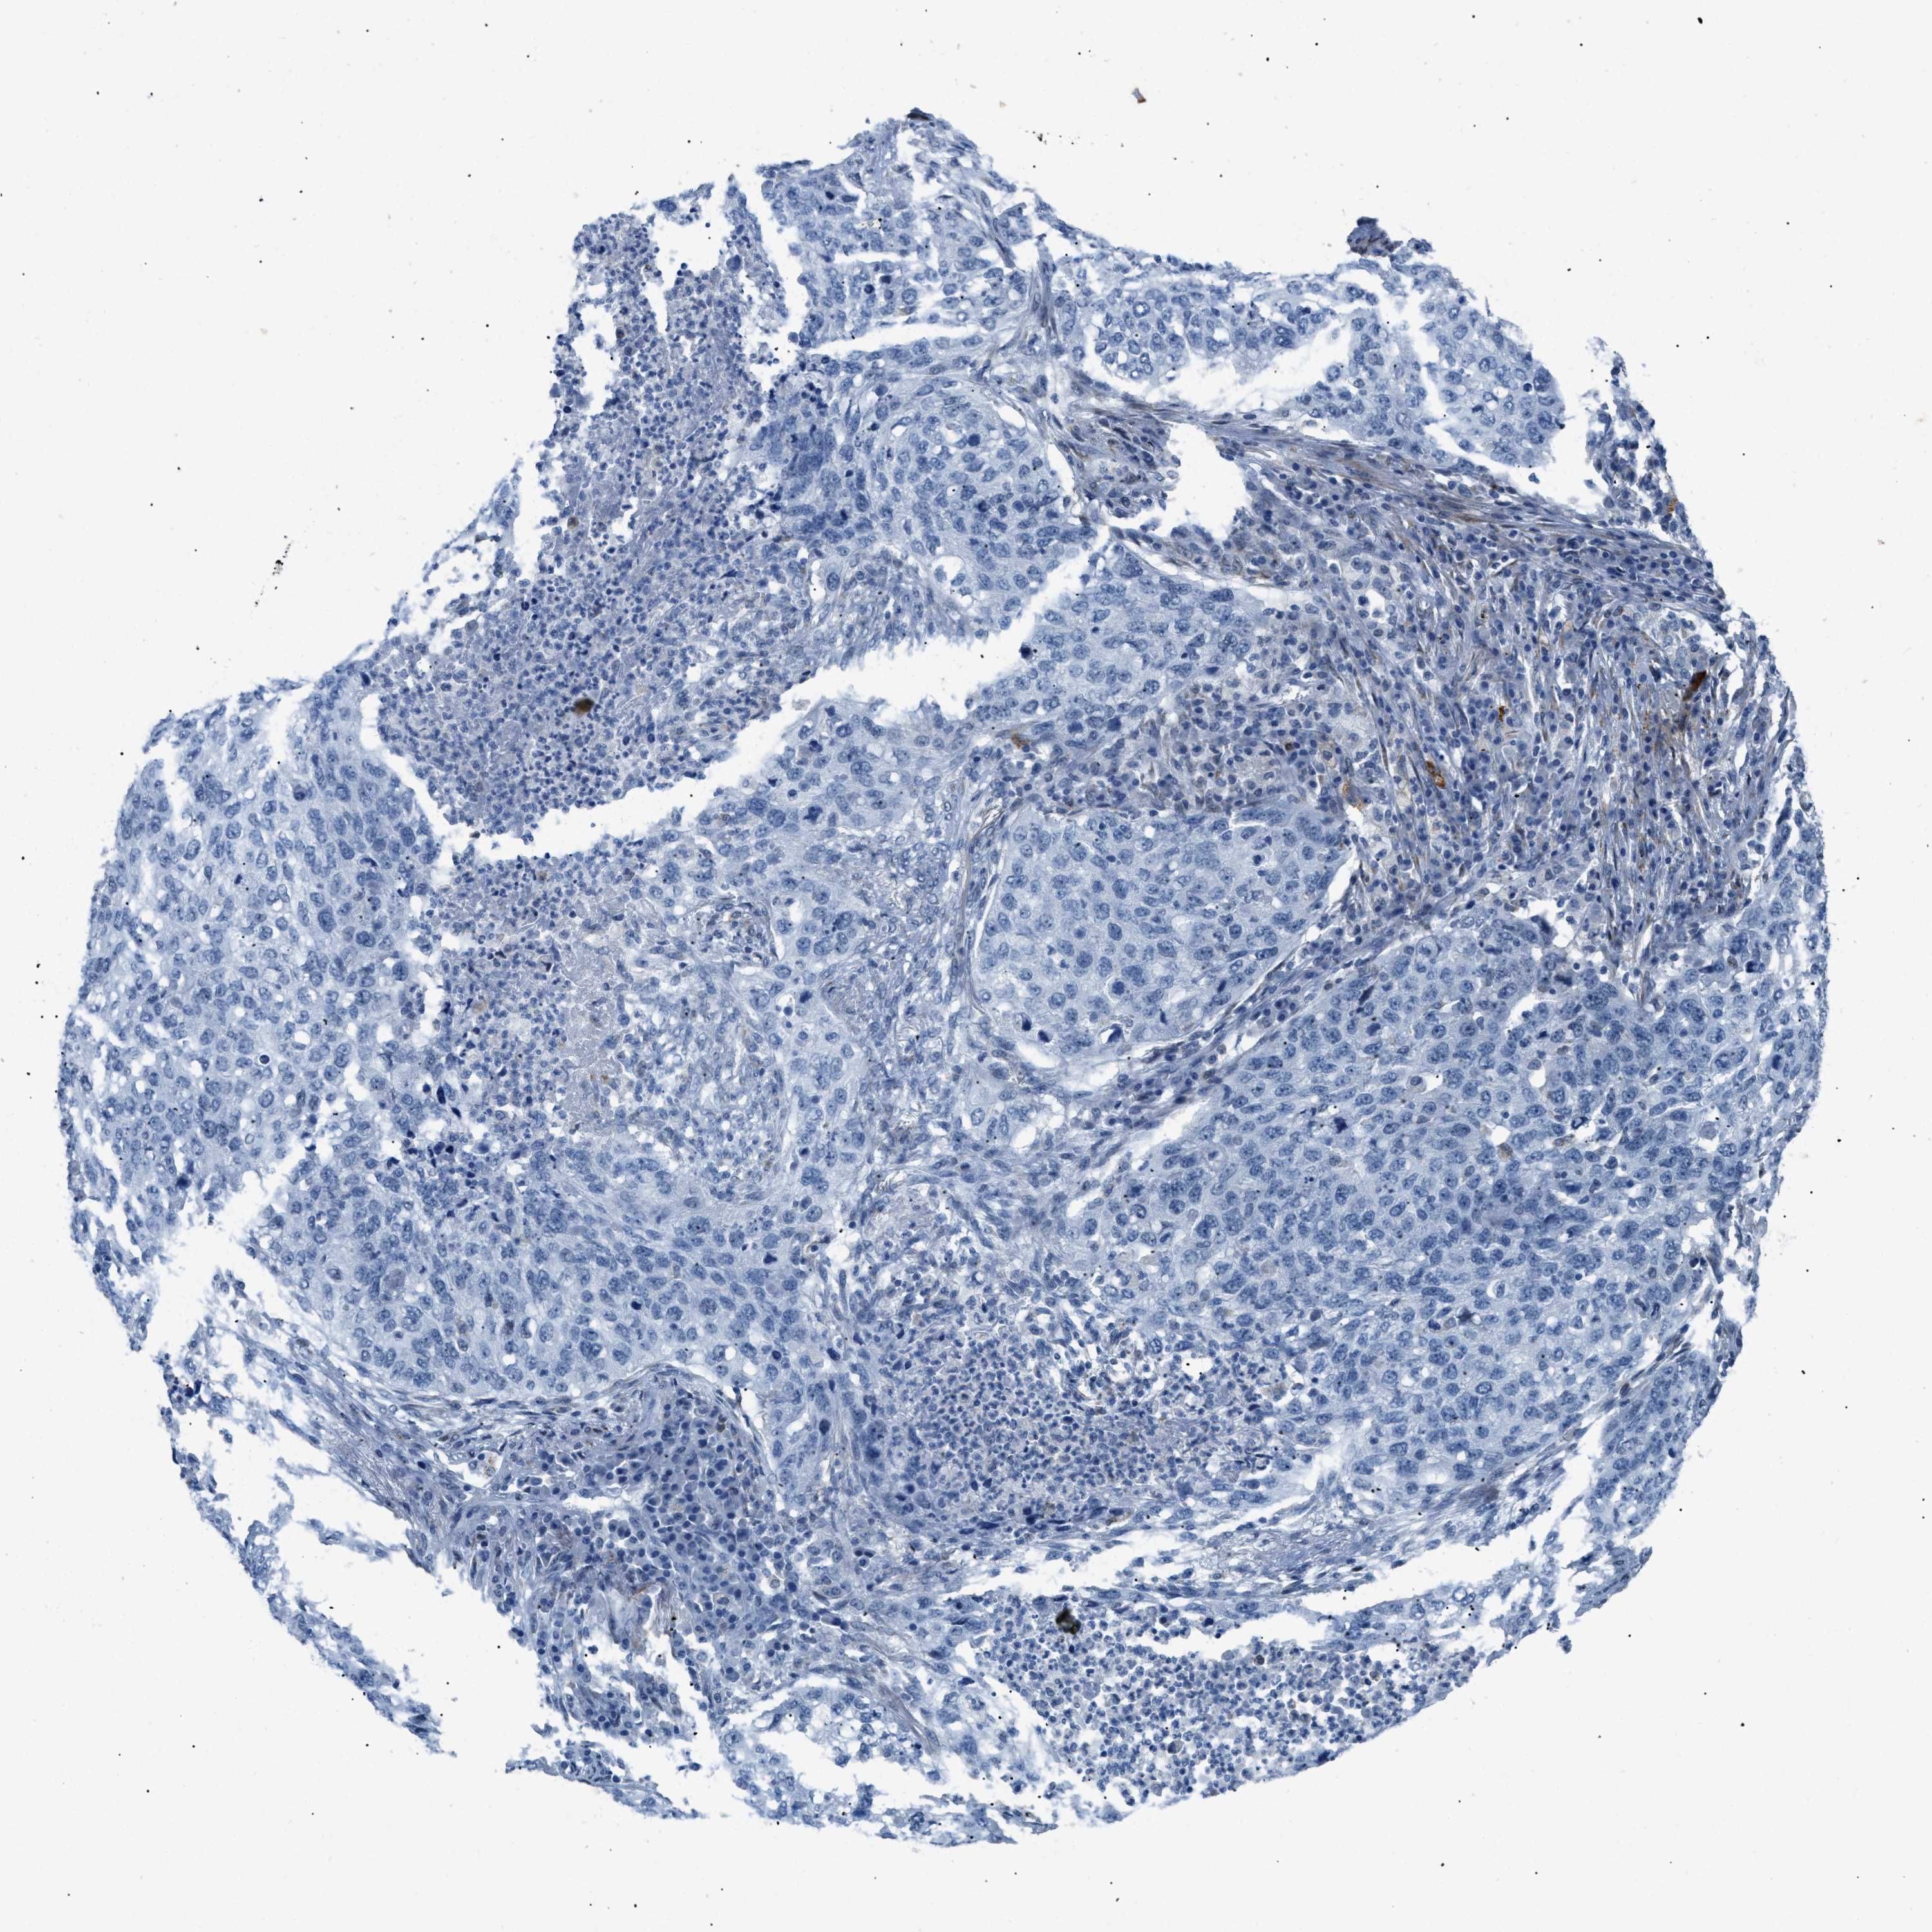

CANCER LUNG CANCER Show tissue menu

Lung cancer

Human cancer

Lung adenocarcinoma

Lung squamous cell carcinoma